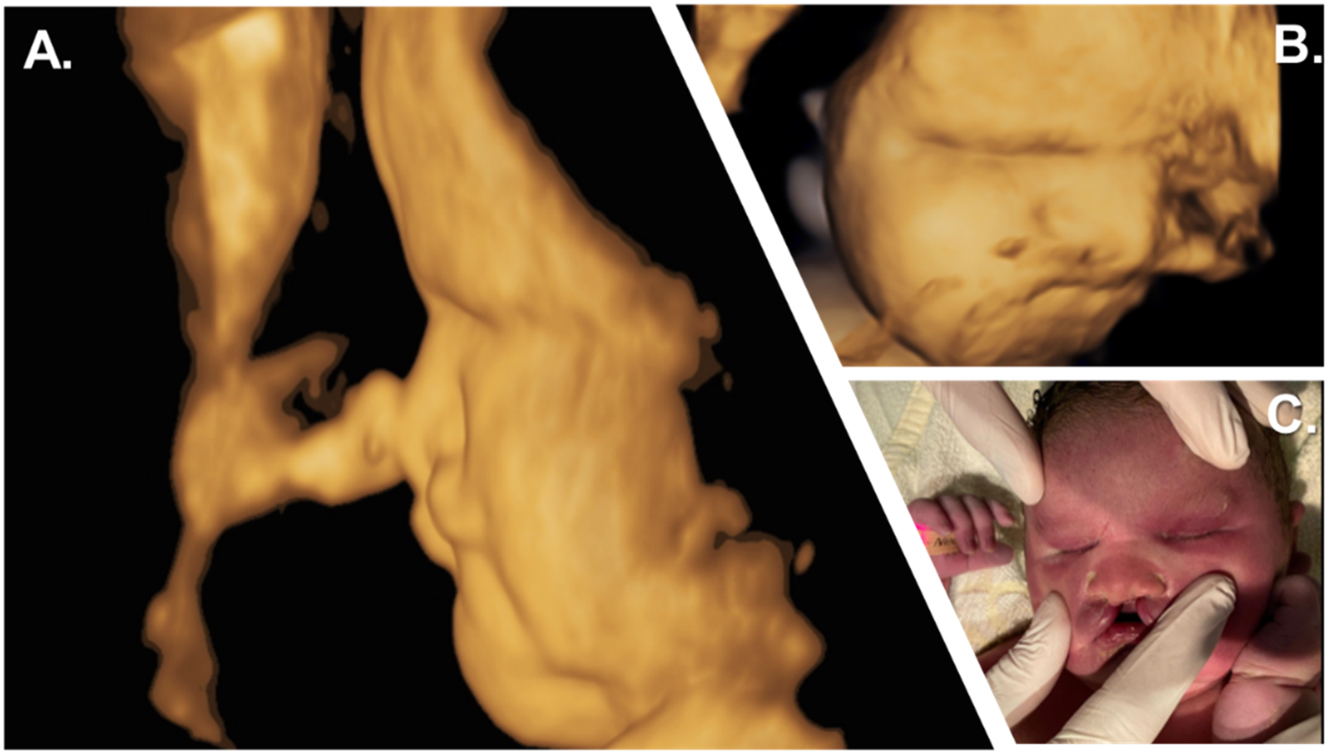

Prenatal and postnatal facial characteristics. (A, B) 3D surface sagittal view of the child’s face at 39 weeks of gestation showing craniofacial hypoplasia with a flat nose. (C) Initial examination showed the neonate’s fused eyelids, bilateral cleft lip and jaw with a suggestive philtrum, complete absence of premaxilla, and total vomer aplasia.

A female child was born post-term, after 43 + 4 weeks of gestation, from consanguineous parents. The mother had a normal antenatal course until 32 + 4 weeks of gestation, when a prenatal sonogram detected bilateral anophthalmia with a cleft lip and palate and craniofacial midline hypoplasia (Figure 1, Figure 2A and B).

After delivery, postpartum sonography and complete ophthalmologic examination confirmed the absence of ocular tissue in the orbits and a complete fusion of the eyelids. The front part of the child’s brain, including the eyeballs and outgoing optic nerves, was not visualized. Clinical examination revealed cleft lips on both sides, midline craniofacial hypoplasia (Figure 2C), and hepatosplenomegaly. Due to several episodes of desaturation, the newborn was admitted to the neonatal intensive care unit for respiratory distress but recovered within a few hours. Repeated cerebral ultrasound failed to visualize a pituitary gland at two days of age. An additional laboratory assessment for endocrinological dysfunction revealed congenital panhypopituitarism. At nine days of age, the newborn presented with severe hypernatremia and polyuria, leading to the diagnosis of central diabetes insipidus. Echocardiography revealed temporary pulmonary hypertension with tricuspid valve insufficiency, right ventricular hypertrophy, and right ventricular dysfunction. Additional abdominal ultrasonography showed hepatosplenomegaly, a disproportionately large uterus, and absent adrenal glands. Further examinations were performed, including chest and abdominal radiography, whole-body sonography, brainstem evoked response audiometry and newborn screening – all revealed normal findings. During hospitalisation, the infant developed two episodes of neonatal infections and icterus praecox, which were treated with antibiotics and phototherapy, respectively. She also presented several episodes of hyperthermia without evidence of either infection or inflammation, which were interpreted as hypothalamic temperature instability retrospectively. The newborn was discharged home at 43 days of age with outpatient ambulatory care.